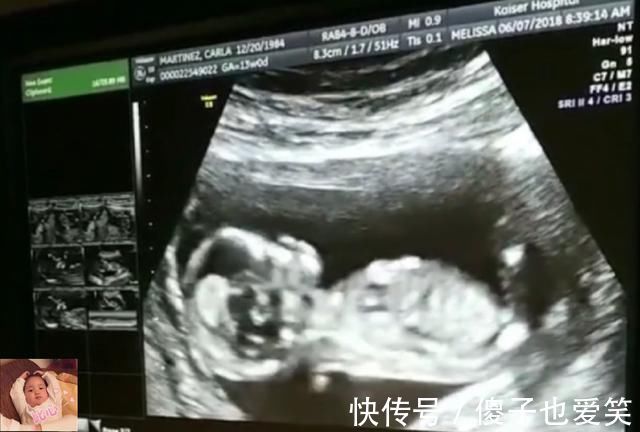

文章插图

1)起床啦

早上伴随着孕妈的起床,16周以后的胎宝宝也会被充足的光线所叫醒的,睁开眼睛,看向有光亮的地方,胎宝宝也正式起床啦。